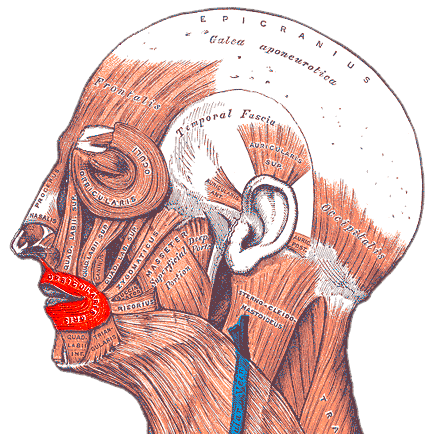

When the uppers sit forward and/or tipped out, the orbicularis oris has to contract to get a seal; that muscle pressure bulges the “central” upper lip so the philtrum reads convex. Your lower lip will catch behind the upper incisors usually (a lip-trap), deepening the labiomental fold too.

View attachment 4176112